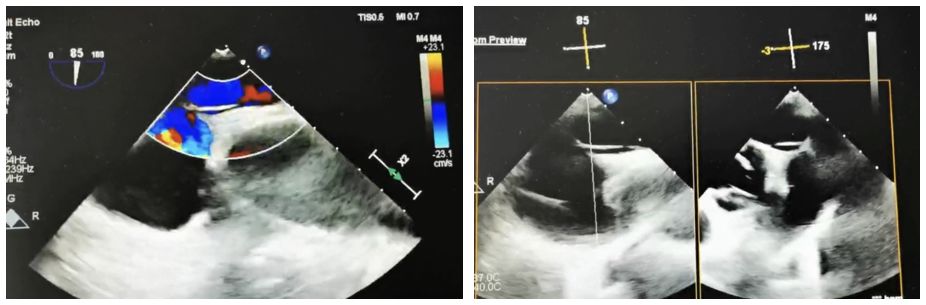

Case Information: A 60-year-old male patient was admitted to the neurology department after experiencing "left-sided limb weakness". The patient underwent a routine transesophageal echocardiogram (TEE), which revealed a patent foramen ovale (PFO) (congenital type, 2.4mm in width, 33mm in length, with moderate shunting). Right heart echocardiography and bubble tests confirmed a grade II shunt.

Strategi klinis: Kami memilih BDPFO-I 2828 occluber simetris untuk memastikan penutupan yang optimal. Selama fase rilis, pencitraan DSA digunakan untuk penentuan posisi, sementara panduan ultrasound terutama digunakan untuk memastikan penyebaran yang akurat.

Ringkasan casing: karena panjang terowongan, panduan kabel kateter konvensional dan dukungan selubung tusukan septal tidak efektif. Secara khusus, kawat panduan koroner digabungkan dengan selubung tusukan septal digunakan dalam kasus ini dan berhasil melintasi septum. Saat menggunakan occluters metalik tradisional untuk penutup PFO terowongan panjang, bahan kaku dan posisi pinggang tetap sering mencegah disk kiri berkembang sepenuhnya. Hal ini dapat menyebabkan cakram ditarik ke dalam terowongan, menyebabkan pengemudian sisa. Sebaliknya, biodegradable occluber, dengan kepatuhan yang kuat, memungkinkan pinggang untuk sepenuhnya mengisi terowongan dan mencapai penutupan yang efektif.